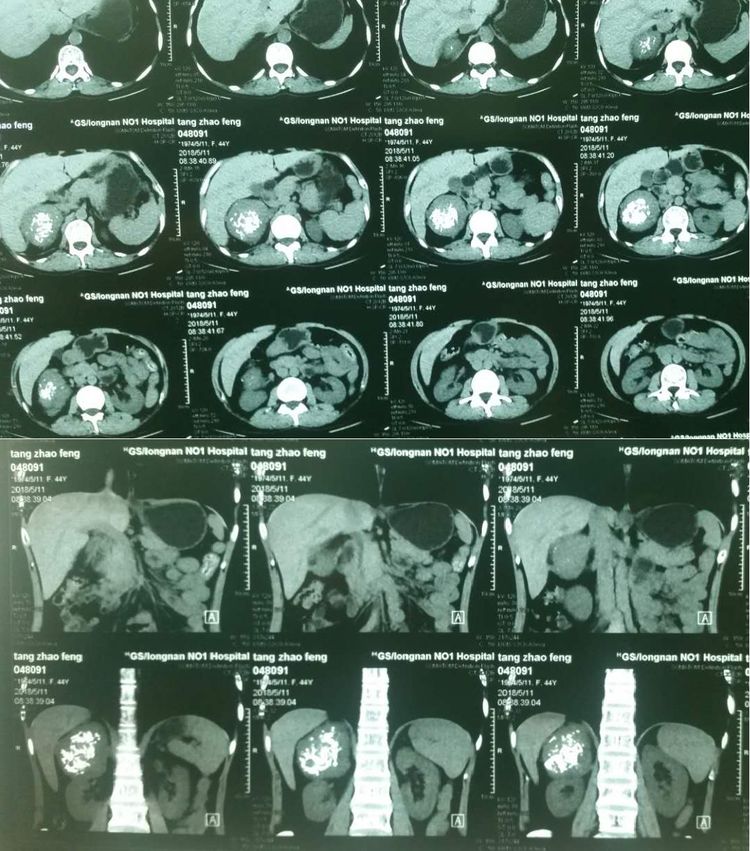

患者女性,44岁,因"体检发现右肾上腺巨大肿物2天"入院。入院后积极完善相关检查,CT平扫显示:患者右肾上腺区直径约6.5X6.1cm肿物,CT值约27-35Hu,中央见多发不规则钙化灶,增强扫描病灶明显强化。

CT平扫见肿物内钙化